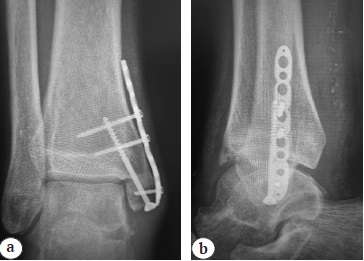

Two weeks after the surgery, the sutures were removed and the wounds healed with primary intension. Continuous immobilization of the ankle joint was performed for 4 weeks to provide adequate integration of the deltoid ligament. Control X-rays were performed, position of the implants was correct and stable (Fig. 6).

Fig. 6. Control X-rays after bone autoplasty and fixation with cancellous screw and plate: a — AP view; b — lateral view